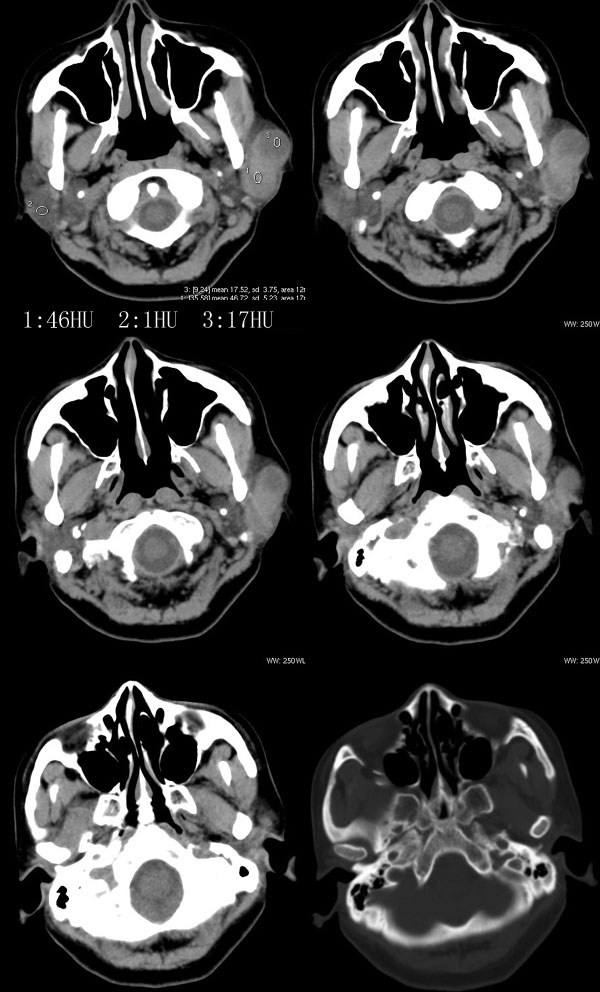

女性,43岁。左腮部肿物5年。体检:(肿物)质中,约5x4x4cm,边界清,固定。

左腮腺肿物,内可见低密度坏死区,增强扫描示肿块明显强化,且呈持续延迟强化,常规考虑腮混合瘤可能性大,但强化表现不太符合,不除外腮腺纤维血管瘤、神经鞘瘤、淋巴瘤及巨淋巴结增生症

强化方式符合:腮腺纤维血管瘤可能性大。另不除外:神经鞘瘤或淋巴瘤!

左侧腮腺多形性腺瘤可能性大。1、是混合瘤中最常见的良性肿瘤;2、中年女性多见并且时间长症状轻;3、病灶内有低密度坏死区,增强时强化;4、其内有钙化,囊性部分未强化;5、需与囊性淋巴瘤相鉴别。